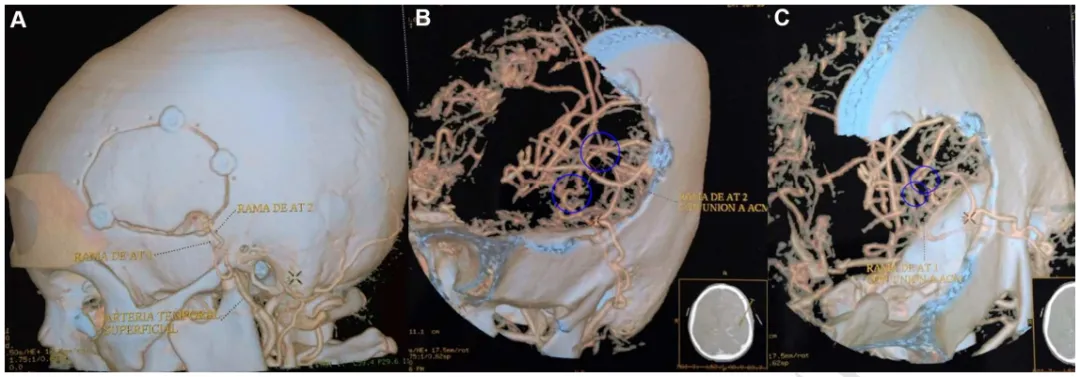

手术采用直接血运重建方式,在显微镜下完成颞浅动脉与大脑中动脉皮质分支的端侧吻合。术中将头皮颞浅动脉仔细分离,与大脑表面选定的大脑中动脉分支进行显微吻合,建立新的脑供血通道。

术后CTA三维重建显示左侧颞浅动脉与大脑中动脉间成功建立两条搭桥血管,手术区域骨窗大小适宜,血管吻合位置精准。